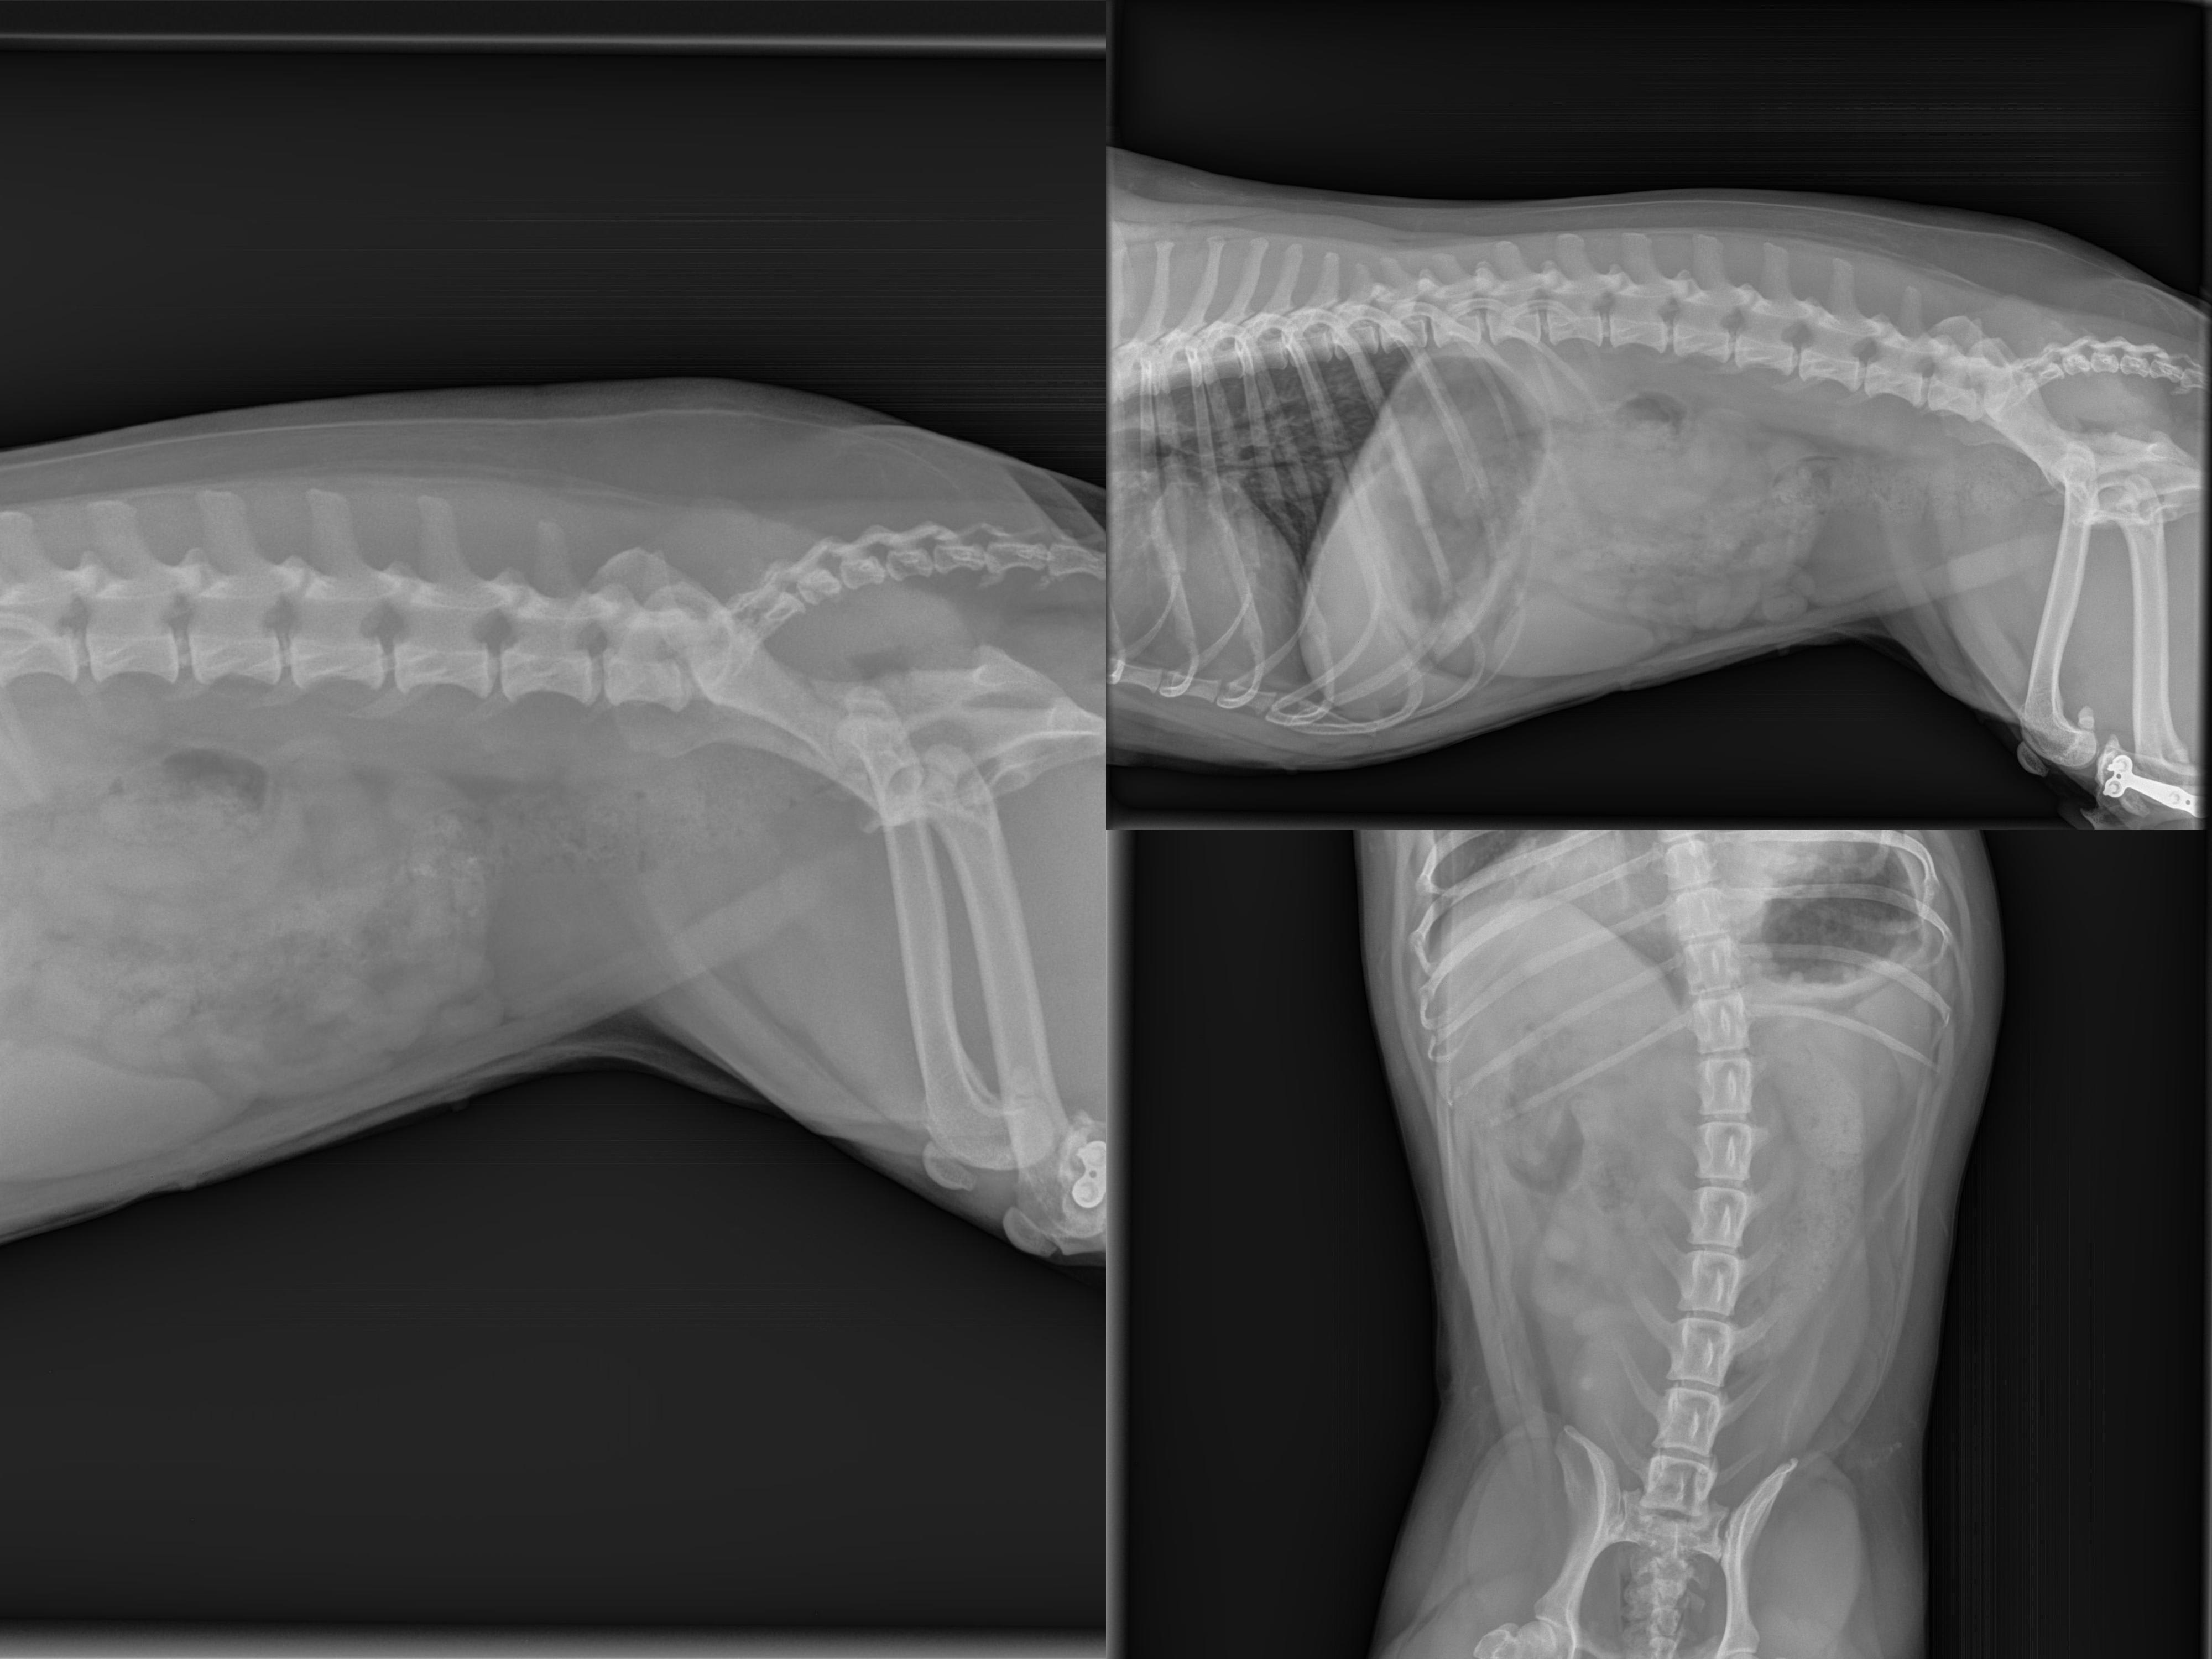

Beatrice display hypomotility, pain, temporary shaking after walking, lip licking and yellow feces. Doctors are unsure if it is enteritis, pancreatitis, or disk herniation. Thank you in advance for your help, Luca

Those are all possible causes. In cases like this, we usually need to treat symptomatically. The normal treatments for pancreatitis would also treat enteritis. Beatrice would need an MRI to determine if she has a herniated disk, but she could be treated with pain medication (which she also needs for possible pancreatitis) in the mean time. I can't tell you which issue is the cause (or they are all a factor) from these images, but I share your vet's concern about all of them.